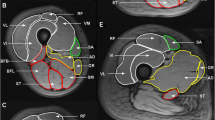

Regions of interest (ROIs) were contoured using Osirix imaging software (version 4.0; open-source DICOM viewer, https://osirix-viewer.com). Regions depicting the individual hamstring and quadriceps muscles were drawn on the middle slice of the in-phase VIBE Dixon volume for each participant, avoiding fascial tissue and subcutaneous fat. ROIs were copied to the corresponding diffusion parameter maps, accounting for differences in image resolution, and the mean value within each ROI was measured. The quantitative MRI slice analysed corresponded to the central slice (slice 20) of the VIBE Dixon muscle volume.

Muscle volume estimates were obtained using a semi-automated algorithm that used fat fraction maps generated from the VIBE Dixon volume data. The algorithm only assigned a voxel as being muscle provided it did not correspond to regions of bone and had a fat fraction of less than 50%. Muscle from the contralateral leg was excluded using a bounding box. Bone was excluded using a 3D-connected components algorithm (bwconncomp, MATLAB) from a seed point manually placed within the bone on the central slice of the VIBE Dixon volume. Finally, a mask defining the muscle was obtained by thresholding, using a fat fraction threshold of < 50% for muscle. This threshold has been previously used in muscle volume measurements in the erector spinae muscles [30]. Muscle masks were only defined between slice 5 and 35 of the 40-slice volume to avoid errors due to signal drop-off at the outer extremities of the receive coil. The volume was defined as the number of voxels in the muscle mask multiplied by the voxel size, multiplied by the slice width.

MRI and muscle function in all participants

Considering the entire 54 participant dataset: (Figs. 2, 3), T2 correlated with flexion (rs = −0.7; p < 0.001), extension (rs = −0.7; p < 0.001) and handgrip strength (rs = −0.6; p < 0.001). FF correlated with flexion (rs = −0.6; p < 0.001), extension (rs = −0.7; p < 0.001) and handgrip strength (rs = −0.6; p < 0.001). MD correlated with flexion (rs = −0.4; p = 0.04), extension (rs = −0.3; p = 0.05) but did not correlate with handgrip strength (rs = −0.1; p = 0.9). FA did not correlate with any of the muscle functions: FA with flexion power (rs = 0.1; p = 0.9), extension power (rs = −0.1; p = 0.1), and handgrip strength (rs = 0.01; p = −0.9). Handgrip strength was also found to be correlated with flexion power (rs = 0.7; p < 0.001) and extension power (rs = 0.7; p < 0.001).

Quantitative MRI and muscle volume and knee flexion and extension correlated with FI and gait speed in older participants (Fig. 4).

In the hamstrings, T2 correlated with FI rs = 0.8; p < 0.001, gait speed rs = −0.4, p = 0.05, knee flexion rs = −0.7, p = 0.01, and in the quadriceps with FI rs = 0.7, p < 0.001, gait speed rs = −0.5; p = 0.007, knee extension rs = −0.6; p < 0.001.

In the hamstrings FF correlated with FI rs = 0.7, p < 0.001, gait speed rs = −0.4; p = 0.02, knee flexion rs = −0.6; p = 0.001 and in the quadriceps with FI rs = 0.7; p < 0.001, gait speed rs = −0.6, p = 0.001, knee extension rs = −0.7; p < 0.001.

In the hamstrings MD was weakly correlated with FI rs = 0.3; p = 0.2, gait speed rs = −0.3, p = 0.1, knee flexion rs = −0.4, p = 0.004 and in the quadriceps with FI rs = 0.4, p = 0.1, gait speed rs = −0.3, p = 0.2, knee extension rs = −0.4; p = 0.007.

Muscle volume (Fig. 5) correlated with FI rs = −0.6; p < 0.001, gait speed rs = 0.6; p = 0.01, knee flexion rs = 0.6; p < 0.001, knee extension rs = 0.6; p < 0.001.

Knee flexion (Fig. 5) correlated with FI (rs = −0.7, p = 0.002), gait speed (rs = −0.4, p = 0.05) and grip strength (rs = 0.7; p < 0.001). Knee extension (Fig. 5) correlated with FI (rs = −0.7; p = 0.001), gait speed (rs = 0.5; p = 0.01) and grip strength (rs = 0.7; p < 0.001).

Handgrip strength correlated with frailty index and gait speed (FI rs = −0.7, p = 0.001, gait speed rs = 0.5, p = 0.06).